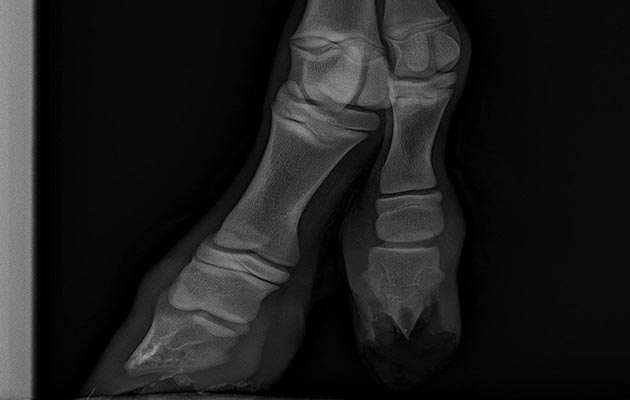

X-rays were taken first to see where it was coming from.

The digit can come from lower down the leg, which requires less invasive surgery, but in this case x-rays showed it came from the carpus (knee).

“Although slightly smaller than a normal leg it was just like any other with fully formed cannon bone, tendons, suspensory ligament, associated joints, blood vessels and nerves,” said Mr Woods.